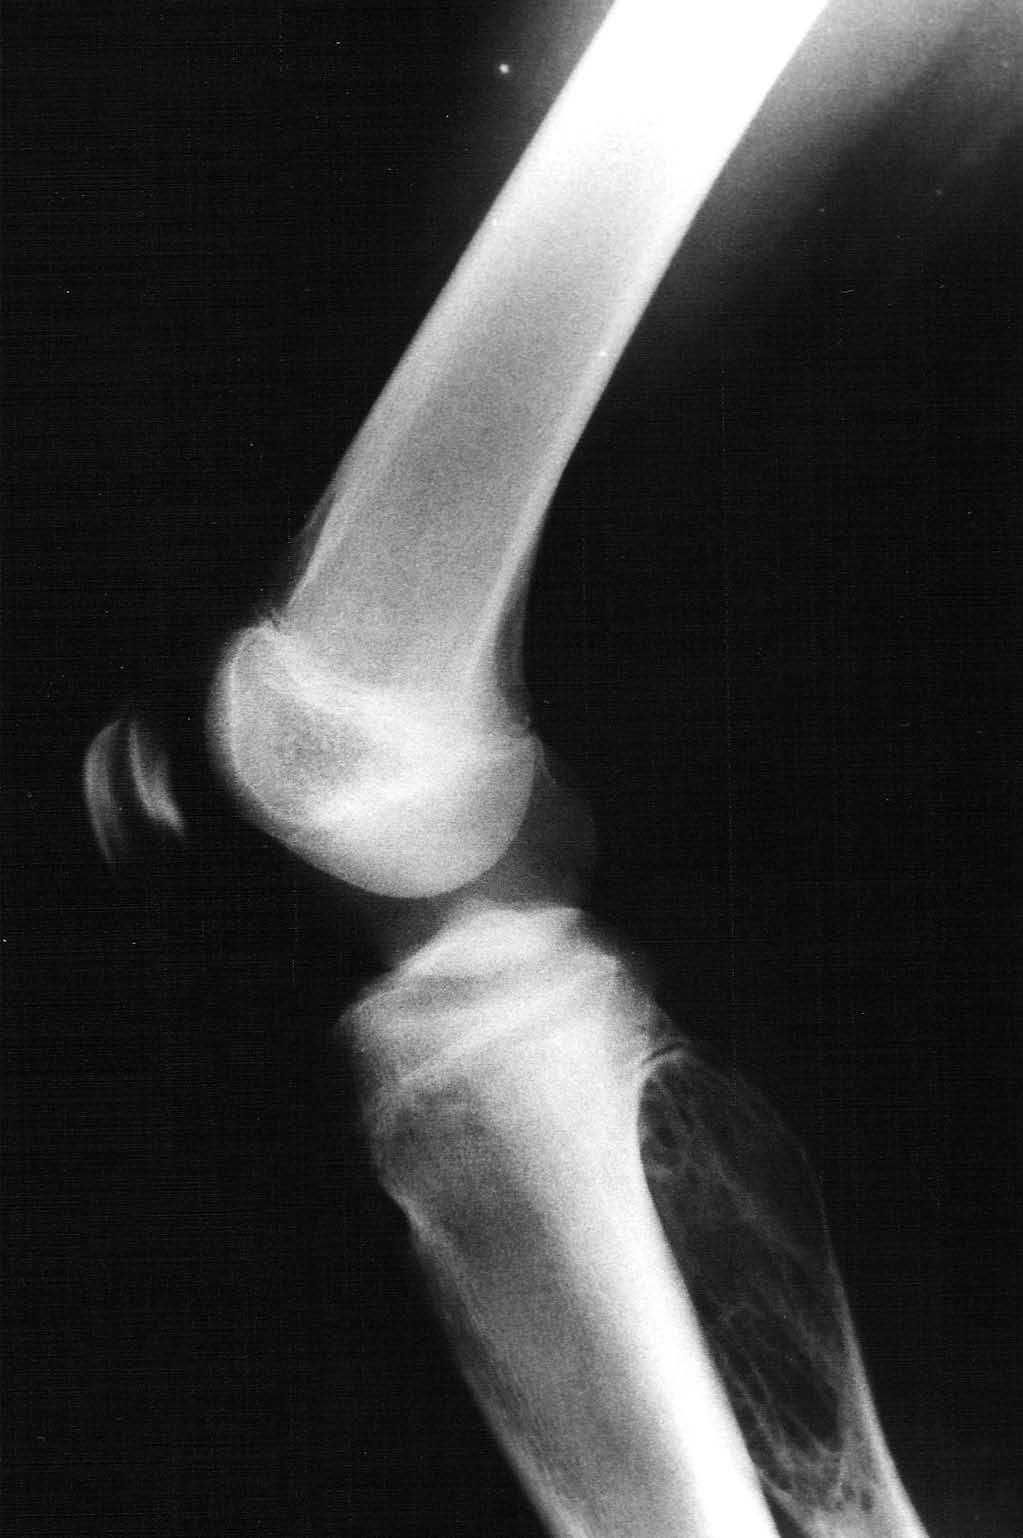

Paciente varón de 15 años, que fue remitido a consultas de traumatología por genu valgo. No tenía antecedentes de interés, salvo crisis asmáticas en la infancia, y la presencia de una lesión lítica ya conocida en el peroné, que sugería el diagnóstico diferencial de displasia fibrosa o quiste óseo aneurismático como primeras posibilidades. La lesión parecía haber crecido respecto a estudios previos. En la radiografía simple (fig. 3), se identificaba una gran lesión lítica expansiva que afectaba predominantemente a la metáfisis proximal del peroné derecho, extendiéndose caudalmente a la diáfisis, y limitada superiormente por la placa de crecimiento. No tenía matriz ósea interna y la zona de transición, al menos en la zona inferior, era estrecha. En el interior presentaba un patrón de múltiples septos con cierto adelgazamiento endostal. En la TC (fig. 4) la cortical estaba muy adelgazada, con focos de discontinuidad sin identificar masa de partes blandas, y presentaba finos septos internos. Se realizó un estudio mediante RM con un equipo de 1,5T (Gyroscan Philips Intera). En la RM el tamaño aproximado de la lesión era de 8,5 x 3,3 x 3 cm (craneocaudal x anteroposterior x lateromedial). La lesión insuflaba el peroné sin visualizar masa de partes blandas. En la secuencia T1-ES (TR/TE 460/15) se comportaba hipointensa de forma homogénea (fig. 5). En la secuencia STIR (1688/15) (fig. 6) parecía tener dos componentes, con diferentes intensidades de señal. El superior hipointenso y el inferior levemente hiperintenso. En la secuencia dinámica T1 (TR/ TE 460/15) tras gadolinio itravenoso (figs. 7 y 8) presentaba un leve realce periférico del componente superior en fase tardía con prácticamente nulo realce en fase precoz y, sin embargo, un intenso realce del componente inferior en fase precoz, seis segundos después de que el contraste se identificase en el interior de los vasos arteriales, con realce persistente en fase tardía (fig. 9). Se realizó una gammagrafía ósea de cuerpo completo en proyecciones anterior y posterior en tres fases. En la fase vascular se observaba un incremento en la llegada del radiotrazador del pool sanguíneo a la región proximal del peroné derecho. La imagen tardía mostraba una hipercaptación en el extremo proximal de dicho hueso. Descartaba la posibilidad de quiste óseo, que no suelen mostrar captación en la gammagrafía y aconsejaban descartar otro tipo de tumoración ósea. No se visualizaron otras lesiones a distancia. En estos momentos el diagnóstico diferencial propuesto fue de fibroma condromixoide, fibroma desmoplásico y quiste óseo aneurismático, a pesar de la ausencia de niveles líquido-líquido. A continuación se realizó una biopsia abierta, con diagnóstico de fibroma desmoplásico. En el estudio macroscópico se identificaban varios fragmentos blanquecinos de consistencia ósea. En el estudio microscópico, se identificó una proliferación de células elongadas, separadas de abundantes fibras de colágeno. La densidad celular era muy variable en función del campo estudiado, lo mismo que la disposición de las fibras de colágeno, bien onduladas o con gran laxitud. Las células tenían núcleos ovoideos, sin aparentes nucleolos y sin figuras mitóticas. Algunos de los remanentes óseos atrapados en la muestra tenían actividad osteoclástica, sin ver en ningún momento atipias.

Fig. 3.--Radiografía lateral de la rodilla derecha. Gran lesión lítica expansiva en la metáfisis proximal del peroné derecho sin halo esclerótico, con septos internos, sin matriz ósea y limitada superiormente por la placa de crecimiento.